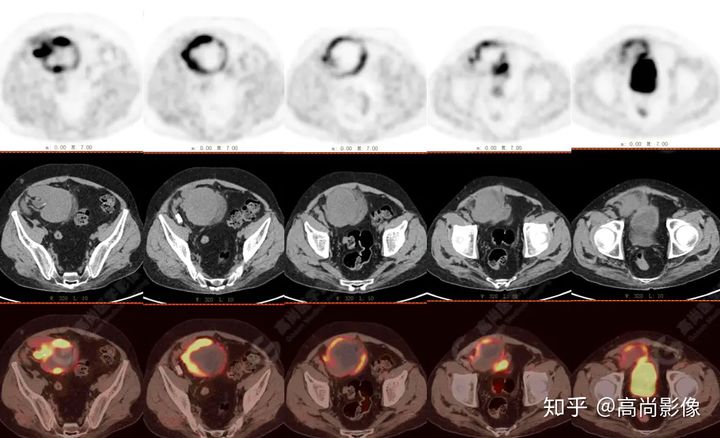

PET/CT檢查

↑移植腎下部等密度腫塊,代謝環(huán)狀增高,SUVmax13.4,中心代謝缺損